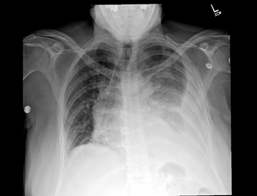

an elevated white blood cell count 14.9 x10^3/uL. CXR did not show any evidence

of acute cardiopulmonary disease. CT scan of the abdomen and pelvis with IV

contrast showed acute pancreatitis with extensive fluid and peripancreatic

inflammatory changes throughout abdomen and possible developing ileus (Figure

1A and 1B). However, no evidence of gallstone or biliary dilatation or

Figure 1A and 1B: CT scan image of showing

inflammation of pancreas (Yellow Star)